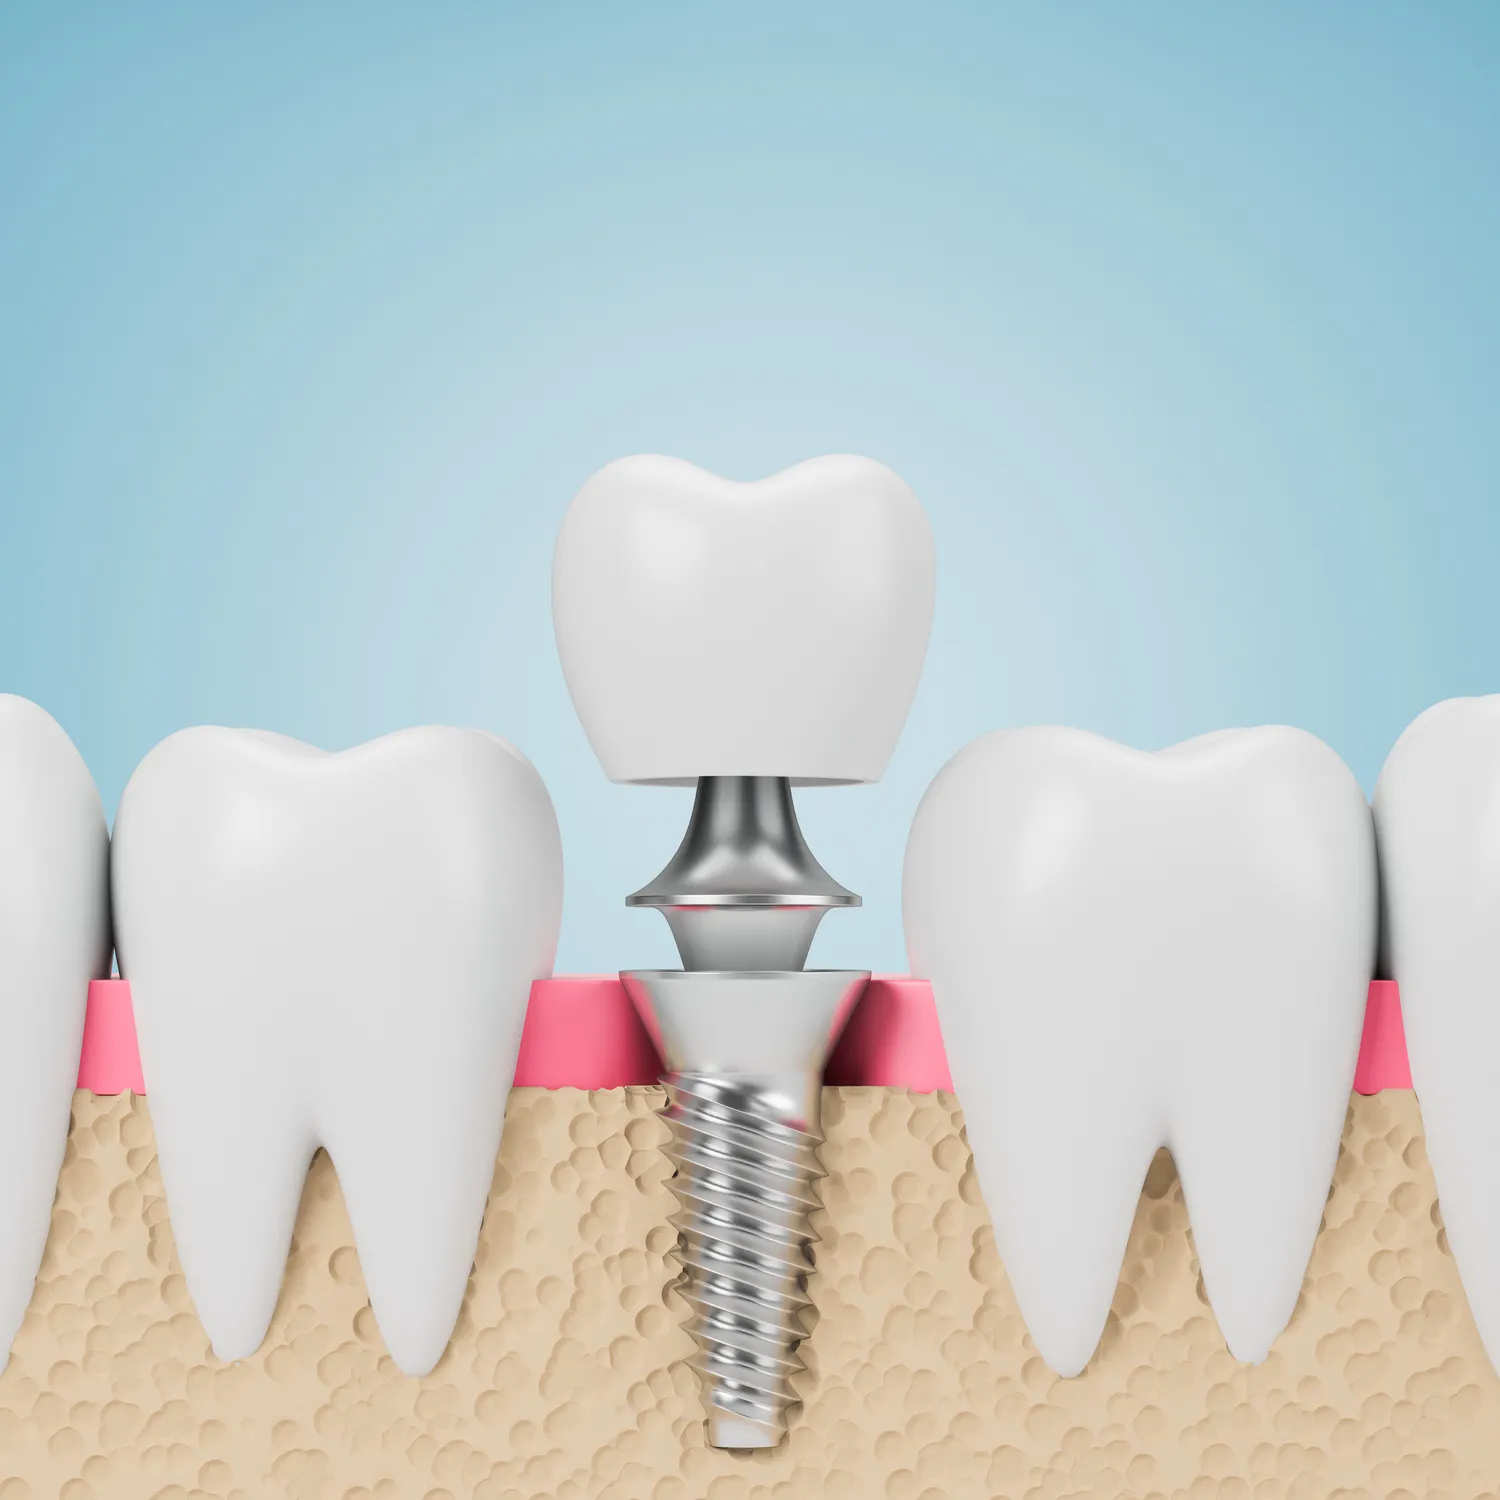

Kliniki implantologii w Lublinie oferują różnorodne metody wszczepiania implantów zębowych, które są dostosowane do indywidualnych potrzeb pacjentów. Najpopularniejszą metodą jest tradycyjne wszczepienie implantu, które polega na umieszczeniu tytanowego słupka w kości szczęki lub żuchwy. W przypadku pacjentów z niedoborem kości możliwe jest zastosowanie przeszczepu kostnego lub użycie implantów typu mini, które wymagają mniejszych ilości tkanki kostnej. Inną nowoczesną metodą jest metoda All-on-4, która pozwala na zamocowanie całej protezy na zaledwie czterech implantach, co znacząco skraca czas leczenia i zmniejsza liczbę koniecznych zabiegów chirurgicznych. Warto również wspomnieć o technologii cyfrowego planowania zabiegów, która umożliwia precyzyjne zaplanowanie lokalizacji implantów oraz minimalizację ryzyka powikłań.

Proces leczenia w klinice implantologii w Lublinie zazwyczaj rozpoczyna się od szczegółowej konsultacji stomatologicznej, podczas której lekarz ocenia stan zdrowia pacjenta oraz wykonuje niezbędne badania diagnostyczne. Na podstawie wyników badań lekarz może zaproponować odpowiednią metodę leczenia oraz przedstawić plan działania. Kolejnym krokiem jest przygotowanie do zabiegu, które może obejmować takie procedury jak oczyszczenie jamy ustnej czy ewentualne przeszczepy kostne. Sam zabieg wszczepienia implantu odbywa się w znieczuleniu miejscowym lub ogólnym, a jego czas trwania zależy od skomplikowania przypadku. Po zakończeniu zabiegu pacjent otrzymuje szczegółowe instrukcje dotyczące pielęgnacji implantu oraz zaleceń dotyczących diety i aktywności fizycznej. W kolejnych tygodniach następuje proces osteointegracji, czyli zrośnięcia implantu z kością, co jest kluczowe dla stabilności całej konstrukcji protetycznej.

W ostatnich latach implantologia w Lublinie znacznie się rozwinęła dzięki zastosowaniu nowoczesnych technologii, które poprawiają efektywność zabiegów oraz komfort pacjentów. Jedną z najważniejszych innowacji jest wykorzystanie cyfrowego planowania zabiegów, które pozwala na dokładne zaplanowanie lokalizacji implantów oraz ich kąta nachylenia. Dzięki temu lekarze mogą uniknąć potencjalnych komplikacji oraz zapewnić lepsze dopasowanie implantu do anatomicznych warunków pacjenta. Kolejną nowością jest zastosowanie technologii CAD/CAM, która umożliwia szybkie i precyzyjne wykonanie koron i mostów protetycznych. Dzięki temu pacjenci mogą otrzymać swoje nowe zęby znacznie szybciej niż w tradycyjnych metodach. Warto również wspomnieć o zastosowaniu materiałów biokompatybilnych, które minimalizują ryzyko odrzutu implantu przez organizm oraz przyspieszają proces gojenia.